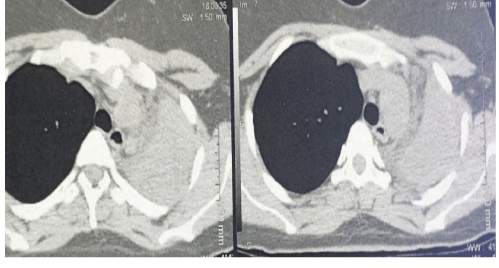

Differential Diagnosis of Asthma: Bronchial Candidiasis.

Benali A*, El Ouazzani H, Rhorfi IR, Souhi H and Abid A.

Bronchial candidiasis are rare respiratory infections whose diagnosis is difficult and often life-threatening, the occurrence of its infections in immunocompetent is rare and it can pose a problem of differential diagnosis with other pathologies such as asthma and bronchial neoplasia...